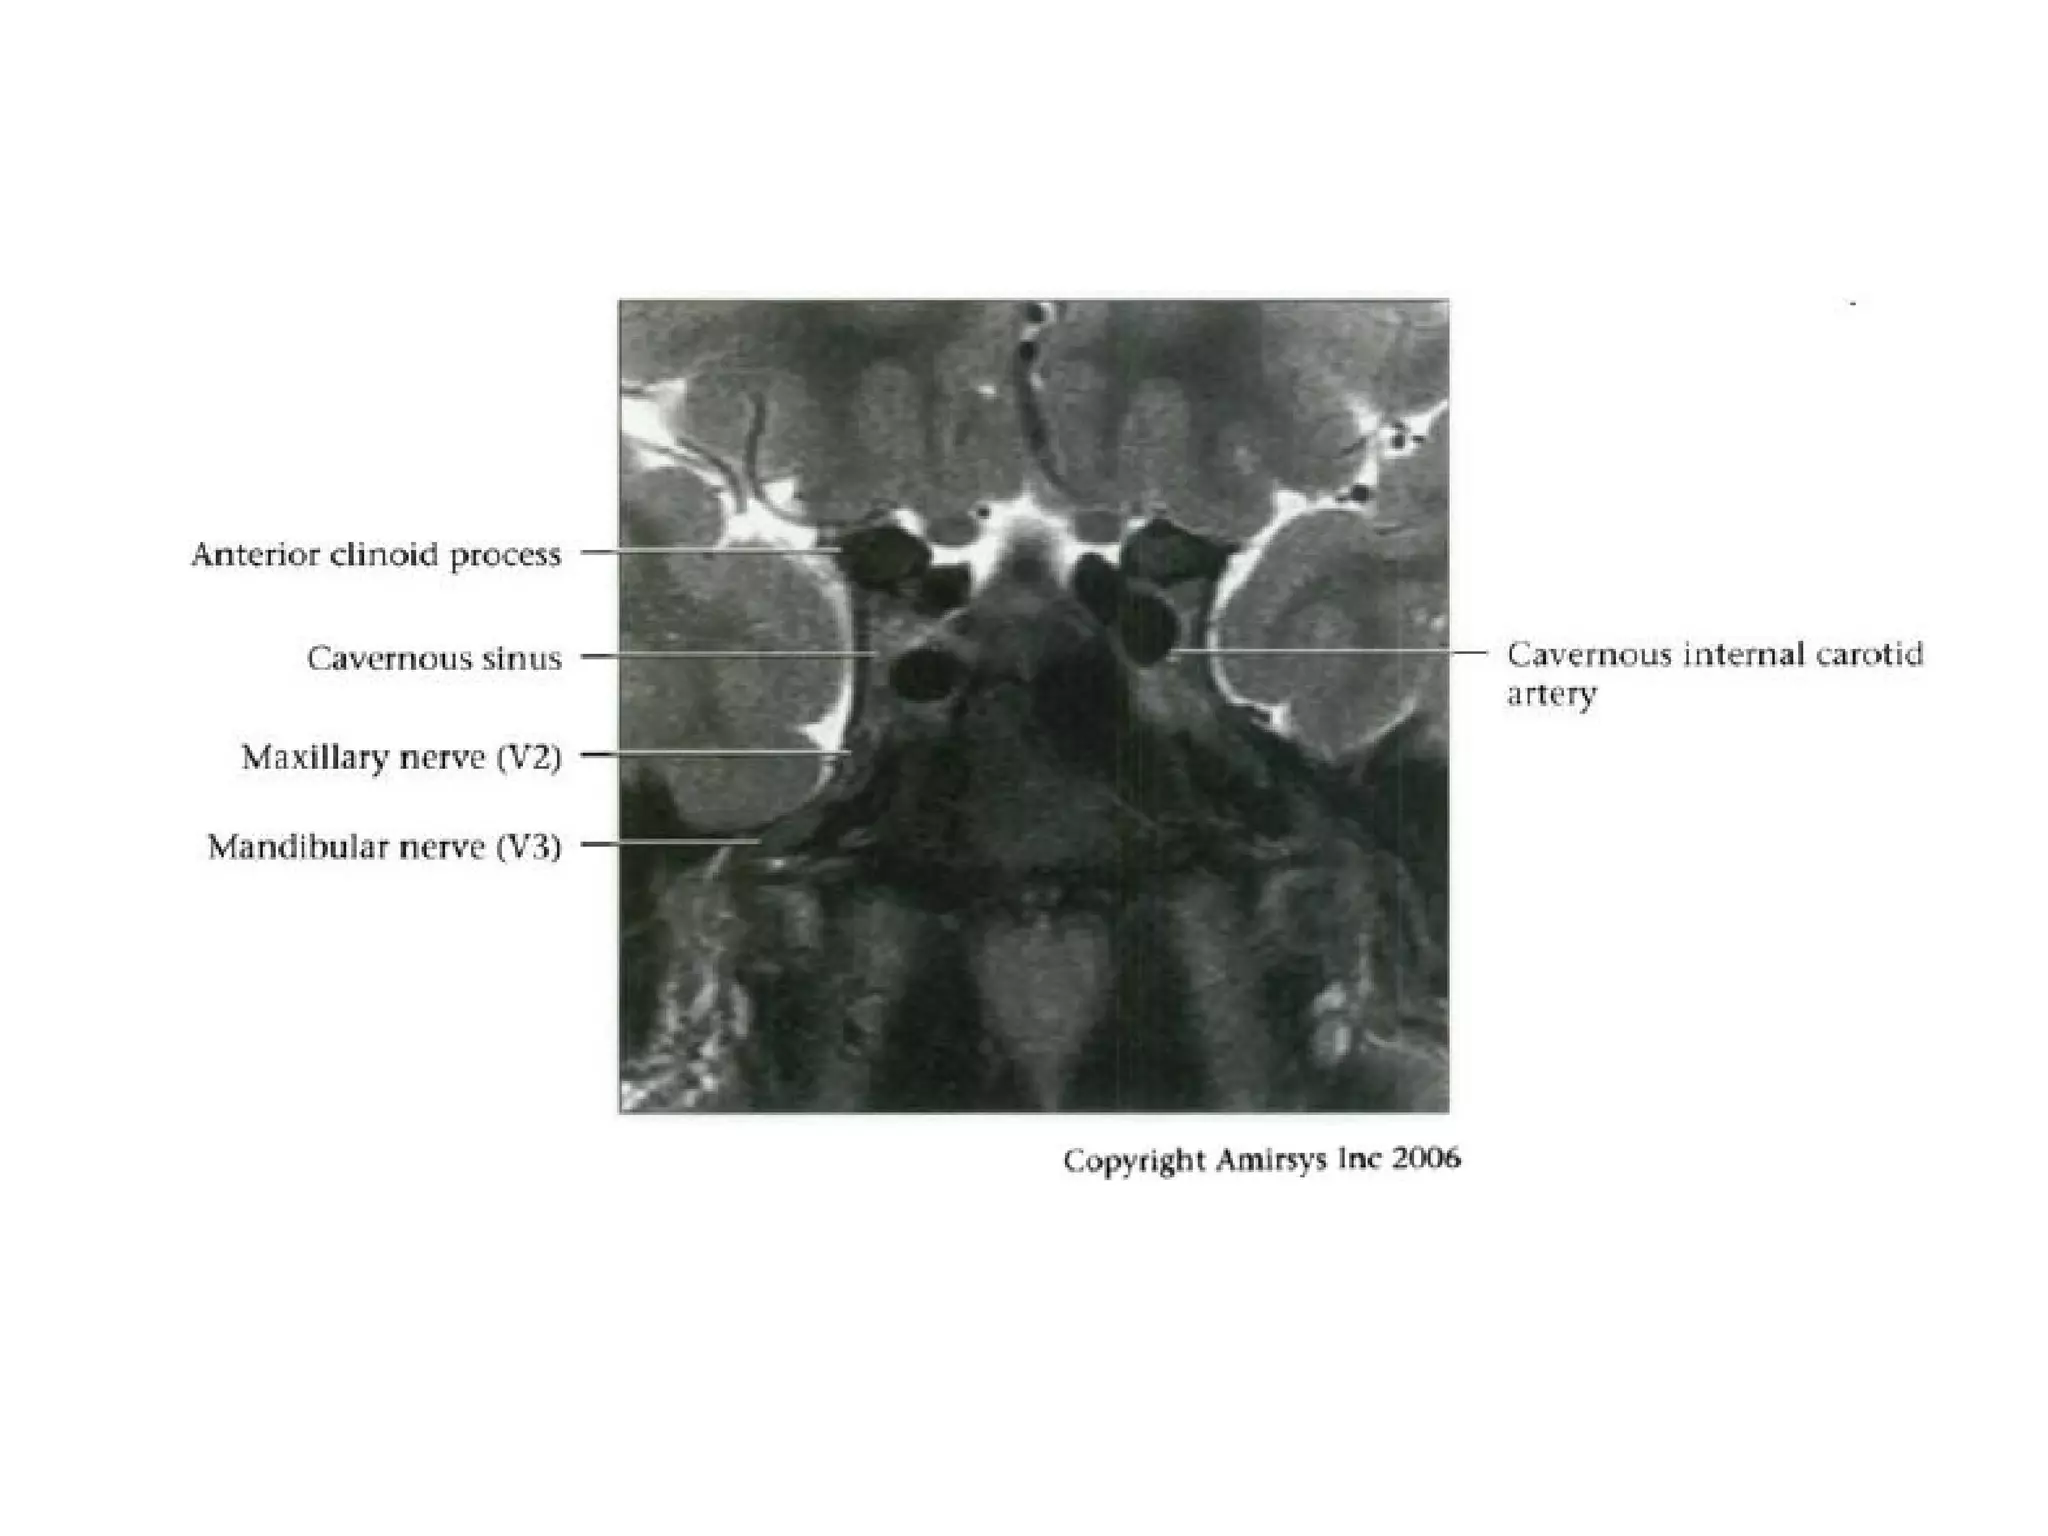

Cranial Nerve V:

The Trigeminal Nerve

• The trigeminal nerve is the largest cranial nerve.

• It is composed of a large sensory root that

runs medial to a smaller motor root.

• The roots emerge from the lateral midpons and

travel anteriorly through the prepontine cistern

and the porus trigeminus to the Meckel

(trigeminal) cave, a CSF-containing pouch in the

middle cranial fossa.

• In the Meckel cave, the nerve forms a meshlike web that

can be visualized only with high-resolution imaging.

• Along the anterior aspect of the cavity, the trigeminal

nerve forms the trigeminal (gasserian) ganglion before

splitting into three subdivisions.

• The ophthalmic (V1) and maxillary (V2) divisions of the

nerve move medially into the cavernous sinus and exit

the skull through the superior orbital fissure and foramen

rotundum, respectively.

• The mandibular division (V3), which includes the motor

branches, exits the skull inferiorly through the foramen

ovale.

RadioGraphics 2009; 29:1045–1055